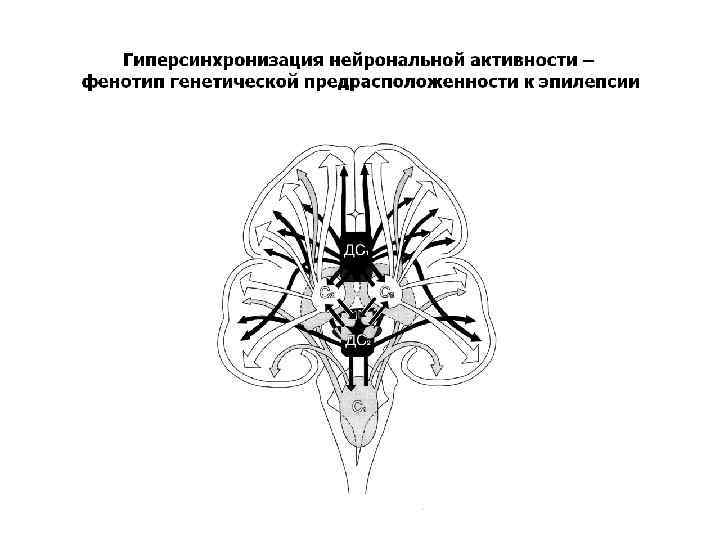

Избыточность возбуждения влечет избыточную синхронизацию, чем определяется роль неспецифических лимбико-ретикулярных структур, в особенности гиппокампа в эпилептогенезе

Генетические факторы эпилептогенеза • экспрессия генов, управляющих рецепторами и ионными каналами мембран нейронов, • продуцирование и динамика нейротрансмиттеров и нейромодуляторов • формирование нейрональной структуры, нейрогенез и апоптоз

Дисбаланс активности возбуждающих (глютамат, N-метил-D-аспартат), передающих возбуждение или торможение в зависимости от типа нейронов (адреналин, норадреналин, серотонин и др. ) и тормозных нейротрансмиттеров (ГАМК).